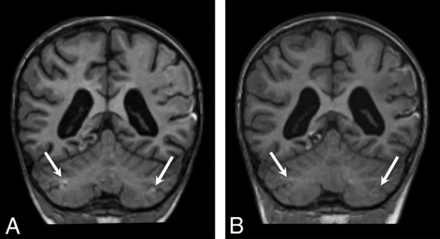

The key imaging feature was T2 and FLAIR hyperintensity and T1 hypointensity confined to the gray matter and immediate subjacent white matter at the depths of the cerebellar fissures (Fig 1). The findings were best seen on coronal and parasagittal fluid-sensitive sequences. In all patients, bilateral hemispheric involvement was present, with injury typically involving multiple fissures centered at the expected location of the borderzone between the superior cerebellar artery (SCA), AICA, and PICA (Fig 2). The cerebellar tonsils were injured in 39% (9/23) of cases. The cerebellar vermis was spared in 91% (21/23) of patients. Five of the 23 patients had prior imaging studies, all of which demonstrated a normal cerebellar cortex (Fig 3).

Axial T2WI from patient 2 (A), parasagittal T2WI from patient 8 (B), and a coronal T2WI from patient 6 (C) demonstrate the characteristic appearance and location of cerebellar watershed injury. There is T2 prolongation greatest in the gray matter at the depths of the cerebellar fissures (white arrows) within the deep cerebellar watershed territory.